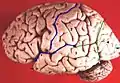

Боковая борозда (лат. sulcus lateralis), также известная как боковая щель (лат. fissura lateralis), латеральная борозда, сильвиева борозда — одна из крупнейших борозд конечного мозга, разделяет лобную и теменную доли от височной доли. В глубине борозды находится островковая доля.

Боковые борозды расположены в обеих полушариях и отделяют височную долю от лобной и теменной. Эта борозда появляется одной из первых уже на четырнадцатой неделе эмбрионального развития[2].

Боковая борозда берет начало на основании мозга и делится на короткую, глубокую, направляющуюся прямо вперед переднюю ветвь (ramus anterior), на направляющуюся кверху и также короткую восходящую ветвь (ramus ascendens) и на заднюю ветвь (ramus posterior), очень длинную, направляющуюся отлого кзади и кверху и разделяющуюся в заднем конце на восходящую и нисходящую ветви[4].

Из-за асимметрии полушарий (Сдвиг Яковлева) латеральная борозда обычно длиннее и менее изогнута в левом полушарии по сравнению с правым.